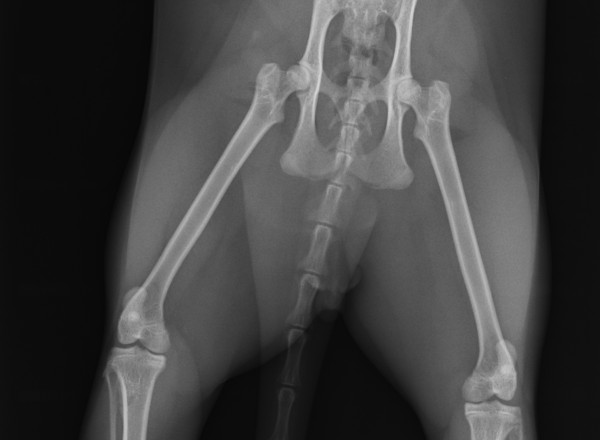

Radiographie Numérique

Radiographie Numérique Sedecal Vet

avec ou sans sédation , suivi radiologique ,

dépistage dysplasie sous sédation